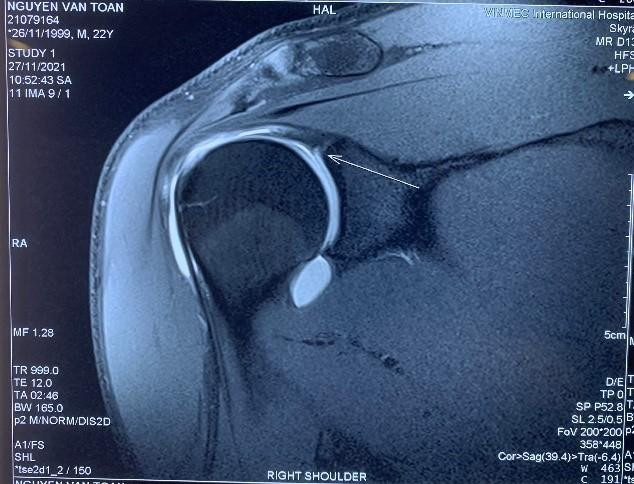

![]() |

| Phim MRI khi có tiêm thuốc thấy rõ tổn thương hơn |

Trong y học thể thao, SLAP là một tổn thương khó chẩn đoán vì vị trí tổn thương nằm rất sâu trong khớp vai. Ngoài ra SLAP có biểu hiện đau nhưng không rõ ràng hoặc chỉ đau ở một vài tư thế nhất định như nâng vật nặng hoặc vận động tay quá đầu… Để chẩn đoán tổn thương này, không thể dùng X - quang hoặc chụp CT mà phải sử dụng chụp MRI có thuốc cản quang để quan sát rõ được các vết rách tại vị trí bám của gân nhị đầu, tránh bỏ sót tổn thương. Tổn thương này cũng cần bác sĩ có chuyên môn sâu thăm khám lâm sàng kết hợp với kinh nghiệm chẩn đoán hình ảnh mới đưa ra kết luận chính xác.

Các bác sĩ cho rằng khả năng đây là tổn thương SLAP vai phải - thương tổn có cơ chế là lực truyền từ cánh tay qua khớp vai đang bị rách, bong khớp, rất phù hợp với kiểu vận động cánh tay đặc thù của thủ môn. Qua phim chụp MRI cản quang và thăm khám lâm sàng, GS Dũng cùng các bác sĩ đã đưa ra kết luận Văn Toản bị chấn thương cơ nhị đầu, cụ thể là bị tổn thương một phần chân bám của cơ nhị đầu cũng như sụn viền chỗ chảo khớp vai.